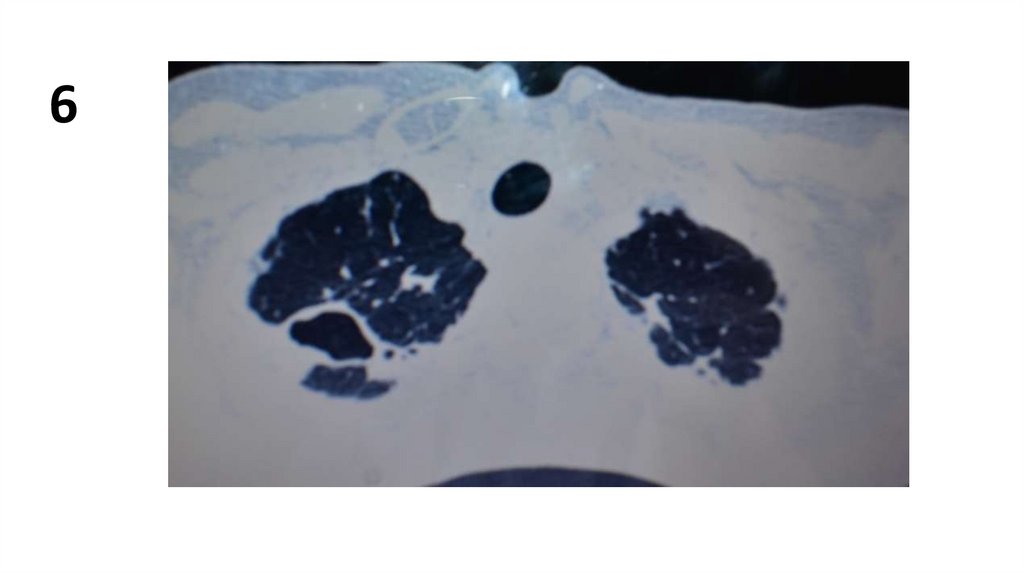

6.

6